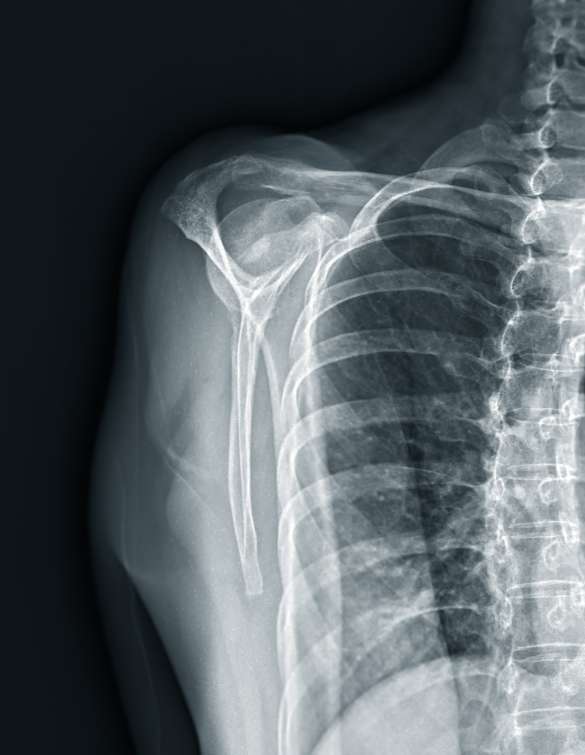

Our center provides comprehensive shoulder replacement services, starting with advanced diagnostics such as digital X-rays, CT scans, and MRI to evaluate joint damage and determine the appropriate type of replacement. We offer total shoulder replacement for arthritis, partial shoulder replacement for isolated humeral head damage, and reverse shoulder replacement for patients with irreparable rotator cuff tears.